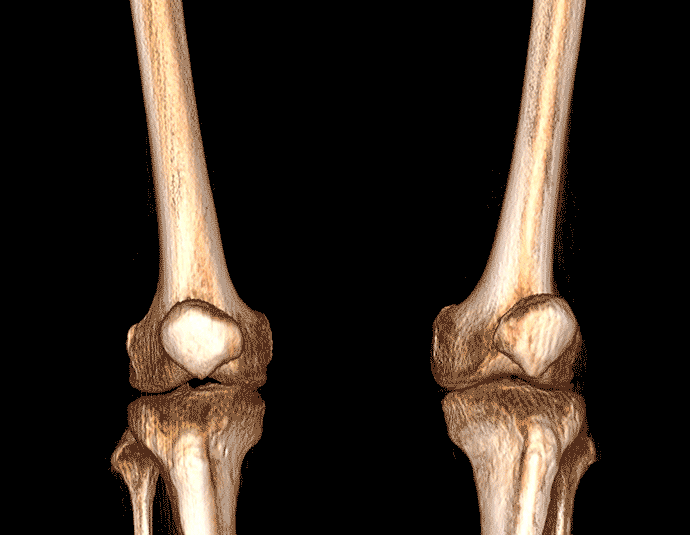

• 膝关节

支持双腿或双侧髋关节扫描 | 方便对比,降低漏诊误诊

FOV 250mm

FOV 350mm